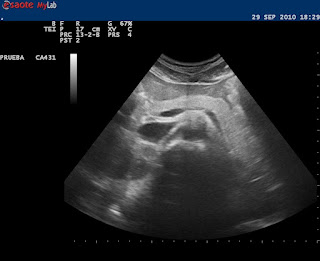

Ha todos ha sorprendido la calidad de la visualización del páncreas de Sara. Pues bien para que tengáis un "recuerdo" os cuelgo una imagen.

Comparaz con vuestros próximos pacientes y no os desaniméis.